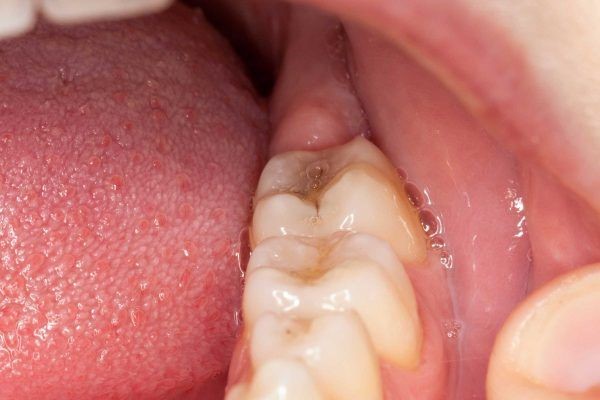

Bạn có thể phát hiện mình đang có răng ngầm thông qua những dấu hiệu sau:

(Hôi miệng, có cảm giác đau nhức, nướu sưng viêm là một trong những dấu hiệu răng ngầm đang mọc)(**)

Răng ngầm là môi trường lý tưởng cho vi khuẩn tích tụ dễ dẫn đến viêm lợi, áp xe, sâu răng và hôi miệng. Một số trường hợp nặng có thể hình thành u nang, làm tiêu xương hàm, thậm chí gây mất răng vĩnh viễn. Vì vậy, việc thăm khám sớm và điều trị kịp thời là rất cần thiết.